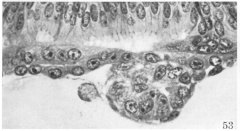

Details of the contact zone